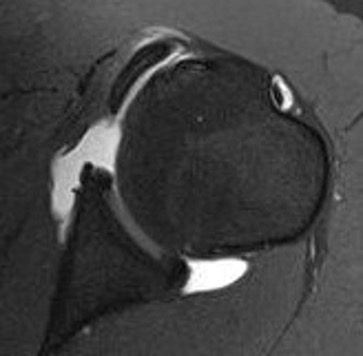

Screw + soft tissue washer

LTLTlt

Medial row anchors and lateral screws for missed lesser tuberosity avulsion in adolescent